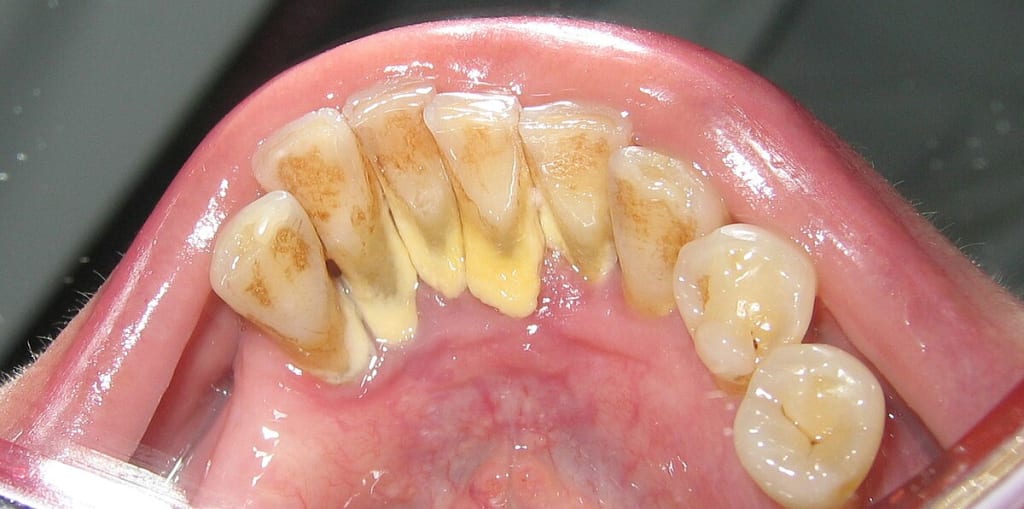

Before diving into the advanced technologies, it's essential to understand what it is. Calculus, commonly known as tartar, is a form of hardened dental plaque. When plaque is not removed through regular brushing and flossing, it can harden and form a rough, porous surface on teeth. This hardened plaque can build up to form a bridge-like structure across multiple teeth, known as a calculus bridge. This condition not only affects the aesthetics of the teeth but also contributes to gum disease, tooth decay, and other oral health issues.